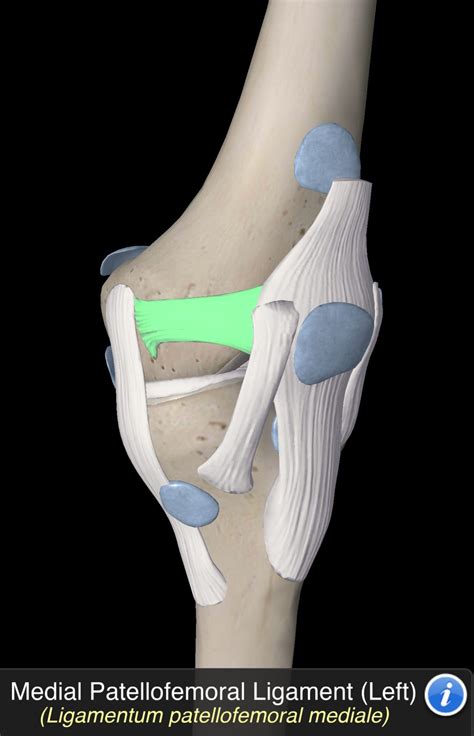

The MPFL is a thin, fibrous band that connects the medial (inner) side of the patella to the medial femoral condyle, which is the rounded part of the femur (thighbone) that articulates with the tibia (shinbone). The primary function of the MPFL is to stabilize the patella, keeping it aligned within the trochlear groove of the femur. This alignment is crucial for the smooth and efficient movement of the knee joint.

The MPFL works in conjunction with other structures, including the vastus medialis obliquus (VMO) muscle, the lateral patellofemoral ligament, and the medial patellotibial ligament, to provide comprehensive stability to the patella. The VMO, in particular, plays a significant role in dynamic stabilization by contracting to pull the patella medially during knee extension.